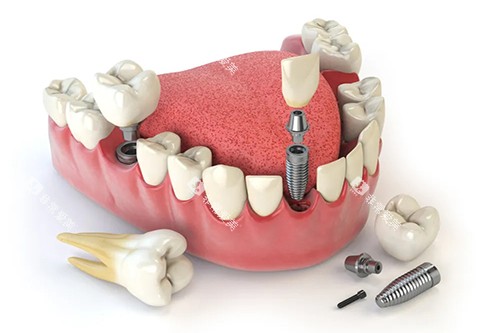

在种牙方面,医院引进了国内外可靠的种植系统,如瑞典诺贝尔种植系统、德国费亚丹种植系统等。

这些种植系统具有稳定性高、生物相容性好等特点,能够为患者提供更优质的种植体验。

医院的种植医生团队经验充足,他们经过严格的可靠培训,具备扎实的理论基础和丰富的临床经验。

在进行种植牙手术前,医生会运用可靠的口腔 CT 设备对患者的口腔状况进行齐全检查,制定个性化的种植方案。

例如,对于一些牙槽骨条件较差的患者,医生会采用骨增量技术,为种植体提供良好的支撑,提高种植可行性。